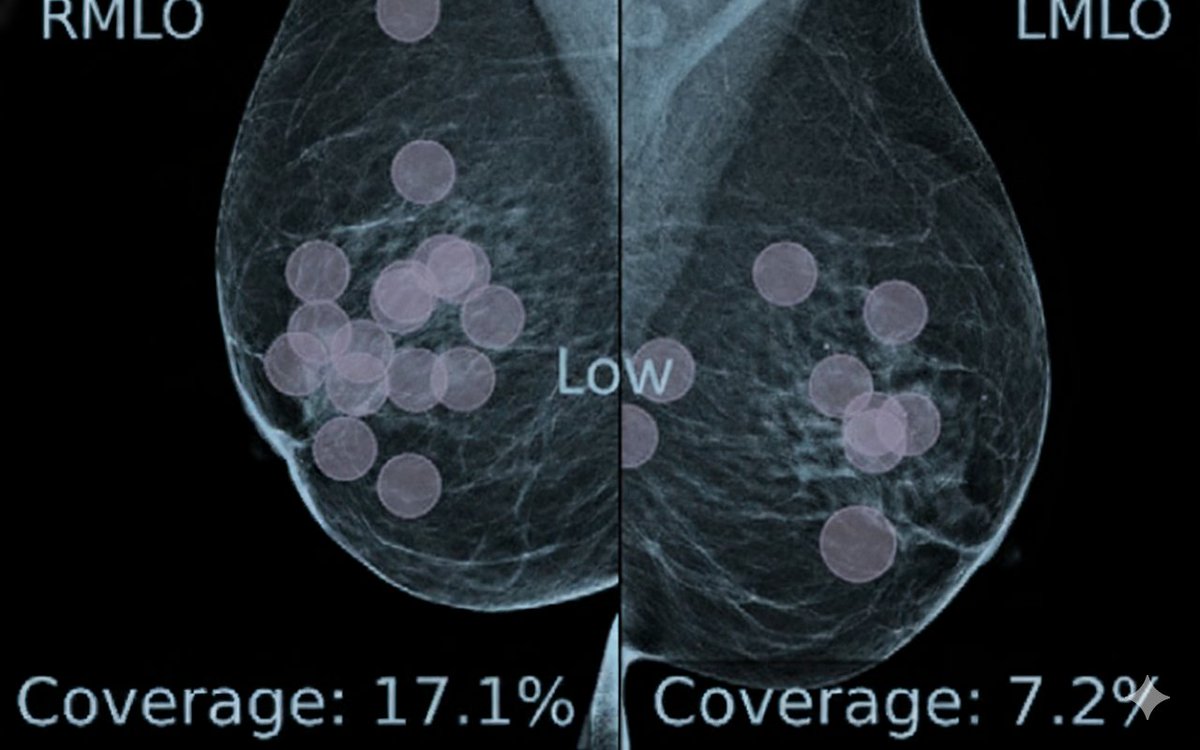

Vision meets Radiology. Two studies, which record eye movements, demonstrate how and why AI can enhance radiologists' search efficiency in mammograms. And how the benefits could be higher for 3D Digital Breast Tomosynthesis. https://t.co/VGC9ldp43E https://t.co/EdJEeJwtsr